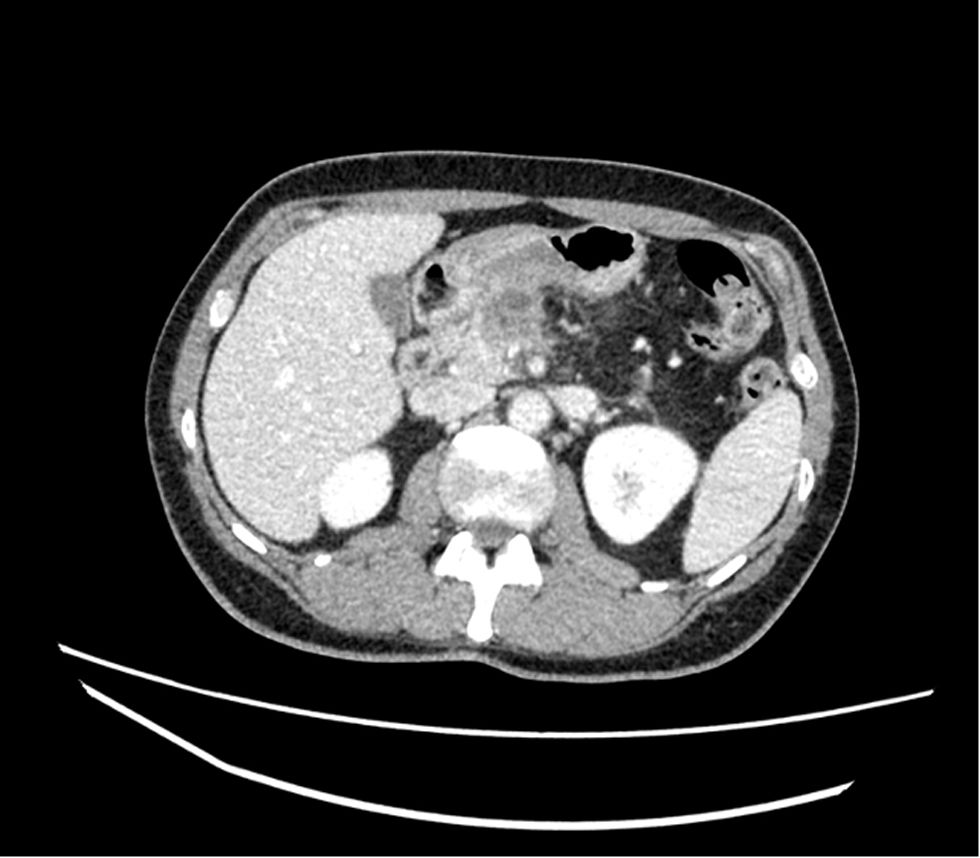

The resection of locally advanced adenocarcinoma of the pancreatic head with occlusion of the superior mesenteric vein and involvement of the splenomesenteric portal confluence (EMP) sometimes requires prolonged venous clamping with risk of intestinal ischemia. The use of intraoperative venous shunts has been published by reference groups to allow successful resection. In our centre we performed a total pancreatoduodenectomy for locally advanced pancreatic head adenocarcinoma with superior mesenteric vein occlusion (SMV) and splenomesenteric portal confluence. The use of a temporary ileo-caval shunt via a venous graft allowed resection of the tumour without repercussion on the bowel. The surgery ended with closure of the shunt, anastomosis of the graft to the portal vein and digestive reconstruction. The patient presented good tolerance to surgery and was discharged on the 7th postoperative day. The pathology report described pancreatic adenocarcinoma ypT1N0(R0) regression grade GRT2/IIa, with 0/30 affected adenopathies.

La resección de adenocarcinoma de cabeza de páncreas localmente avanzado con oclusión de la vena mesentérica superior y afectación del confluente esplenomesentéricoportal (EMP) obliga en ocasiones a un clampaje venoso prolongado con riesgo de isquemia intestinal. La utilización de shunts venosos intraoperatorios ha sido publicado por grupos de referencia para permitir la resección con éxito. En nuestro centro realizamos una duodenopancreatectomía total por adenocarcinoma de cabeza de páncreas localmente avanzado con oclusión de vena mesentérica superior (VMS) y confluente esplenomesentéricoportal. El uso de un shunt ileo-caval transitorio mediante un injerto venoso permitió la resección del tumor sin repercusión en el intestino. La cirugía finalizó con el cierre del shunt, anastomosis del injerto a la vena porta y reconstrucción digestiva. El paciente presentó buena tolerancia a la cirugía, siendo dado de alta el 7 ° día postoperatorio. El estudio anatomopatológico describió adenocarcinoma pancreático ypT1N0(R0) grado regresión GRT2/IIa, con 0/30 adenopatías afectas.